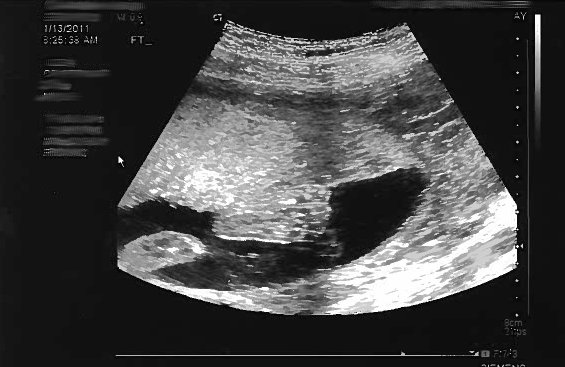

13 January 2011 – Another FANTASTIC day! You had your “big” photo shoot!

Mom & Dad went to this super cutting-edge, hi-tech medical appointment. The person in the medical office used a magic wand on Mom’s belly to create images of you inside.

It was your 20-week “ultrasound” (or “Fetal Survey” as they say in the obstetrical world). Basically they used cyclic sound pressure with a frequency greater than the upper limit of human hearing. Although this limit varies from person to person, it is approximately 20 kilohertz (20,000 hertz), but you know this already, of course.

Mom had SUCH a fun time seeing the detail that goes into the ultrasound and your dad asked so many questions. Being that your mom works closely with the perinatology office that did the ultrasound, your parents felt they got a little VIP treatment during the appointment. One of your mom’s favorite perinatologists, Dr. Harding, read the ultrasound and was happy to tell us you look PERFECT! The ultrasonographer, Allison, said you should be in a textbook, which made your dad VERY proud. Your mom jokingly reminded your dad that being in medical textbooks isn’t always a good thing… but we know you’re happy and healthy in there!